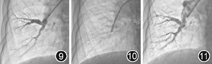

因规范药物治疗效果不佳,建议行PEA手术治疗,但患者考虑PEA术风险大,拒绝接受。建议患者行PTPA术并告知手术风险,患者及家属同意并签署手术同意书。行右心导管检查,具体数据见表1。术前根据术前肺通气/灌注检查结果提示右上肺和双下肺通气灌注缺损明显区域作为治疗部位,送入5F猪尾导管行双下肺野多体位选择性肺动脉造影确定病变血管确定病变部位(图9,图10,图11)。沿导丝送入6F MPD及6F JR3.5指引导管采用子母技术,将指引导管置于靶血管开口,送入贯穿导丝置于血管远端,沿导丝送入C7 Dragonfly OCT图像采集导管行OCT检查,可见管腔内大量网状结构,管腔狭窄(图12)。回撤OCT成像导丝,送入Pressurewire置于血管行压力测定,狭窄近端压力86/14/39 mmHg、狭窄远端压力16/7/11 mmHg,PPR(Pd/Pp):0.25。使用Cordis 3.0×15 mm球囊压力8~12个大气压维持8~10 s于病变部位扩张,扩张后造影血流明显改善,局部肺静脉回流明显增多增快。再次送压力导丝及OCT成像导丝,OCT成像导丝可见网格样结构被撕裂、管腔较前增宽(图13);分别测量压力,狭窄近端压力86/8/34 mmHg、狭窄远端压力33/8/14 mmHg,冠状动脉血流储备分数(fractional flow reserve,FFR)为0.44(图14,图15,图16,图17)。为避免再灌注肺水肿,初次在右上叶和双下叶肺野选择3条血管进行扩张,术毕拔除股静脉鞘管,加压包扎。术程顺利,患者无咯血、恶性心律失常。术后严密观察48 h,未发生灌注肺水肿。术后患者活动后气促症状改善。出院治疗方案为他达拉非10 mg,1次/d,贝前列素钠20 μg,3次/d,利伐沙班20 mg,1次/d。1个月后复查右心导管检查(表1),再次行右上及左下肺动脉球囊扩张(表2)。手术过程同上,术中和术后患者无咯血、无灌注肺水肿发生。术后患者活动后气促症状明显改善,6 min步行距离延长,行肺通气/灌注检查发现治疗后右上肺和左下肺灌注较前改善(图3,图4,图5,图6,图7,图8)。出院治疗方案为他达拉非10 mg,1次/d,利伐沙班20 mg,1次/d。

注:图9可见右下肺动脉基底段多发狭窄;图10示球囊扩张狭窄肺动脉;图11球囊扩张后复查发现右下肺动脉血流明显改善,肺静脉回流增多增快